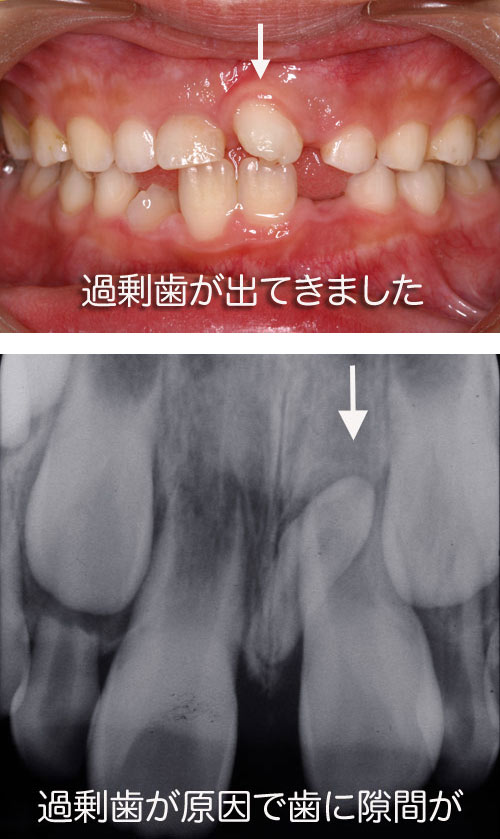

12.上の前歯のところに尖った歯が出てきた

上の前歯の真ん中に過剰歯が出てくる場合があります素人が見ても形がおかしいのでびっくりしますがこれは普通の永久歯ではなく余分に生えてくる歯なので抜いておく必要があります。あまり抜く時期が遅くなると前歯に隙間ができてしまう場合があるのでお子さんが抜歯に耐えられるのであれば早めに抜いてしまった方が良いでしょう。